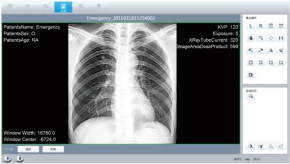

6 | 一体化图形采集处理工作站 (品牌:七喜)

| 1、型号:HMS-003 品牌:七喜 2、Windows 操作系统; 3、CPU:i5-4590/3.3GHz 4、内存容量:8G 5、硬盘容量:1T 6、接口:标准DICOM 7、图像显示器:24寸显示器 8、信息管理 a) 病人录入功能; b) 摄影检查功能; c) 图像浏览功能; d) 数据管理与传输功能; e) 通过网络进行DICOM格式的影像传输; f) 诊断报告打印功能; g) 体位摆放示意图:128个; h) **可编程APR:2000; 9、窗宽、窗位和Gamma调节,多点LUT曲线调整正负片转换、图像缩放、平移、镜像、旋转、放大镜显示;图像平滑、锐化、降噪、提取边缘、组织均衡;图像标注功能,包括画直线、矩形、多边形、箭头和文字;图像原始显示、全屏显示、直方图显示、不同部位窗宽窗位预置;实时提示系统可存储的图像数量; 10、数字摄影功能,可配置正负片图像采集;实时窗宽窗位调节;实时ROI裁剪;实时水平镜像、垂直镜像、旋转功能,根据不同部位选择镜像和旋转;可显示病人信息/检查信息/设备信息/图像信息; 11、支持扫码**扫码登记、身份证、社保卡阅读器(支持大批量表格导入病人信息) 12、支持大批量导出病人片子 13、自动保存病人片子并按日期文件夹自动归档。 14、赠送报告软件:中文诊断报告编辑,自定义报告格式,所见所得。(提供诊断报告模板,短语,任意安排)并可直接打印诊断报告 |